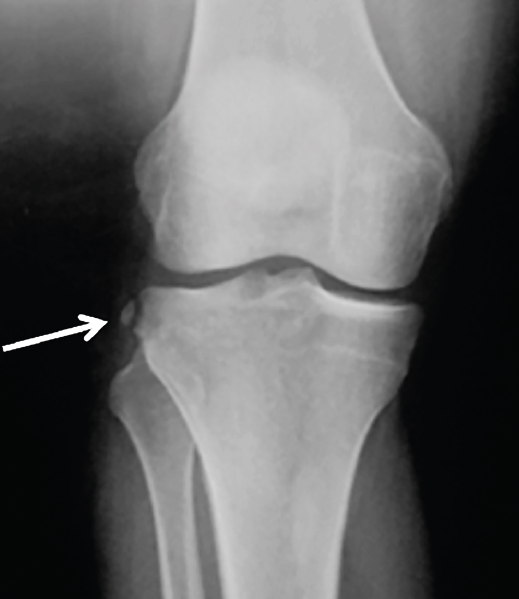

Figura 2. Radiografía anteroposterior de una rodilla derecha, donde puede apreciarse una fractura de Segond (flecha blanca).

- Radiografía (Rx): la imagen radiológica más característica que se relaciona con la lesión del LAL es la fractura de Segond, aunque esta solo está presente en un 1,25% de los pacientes con lesión de LCA(34)(Figura 2).